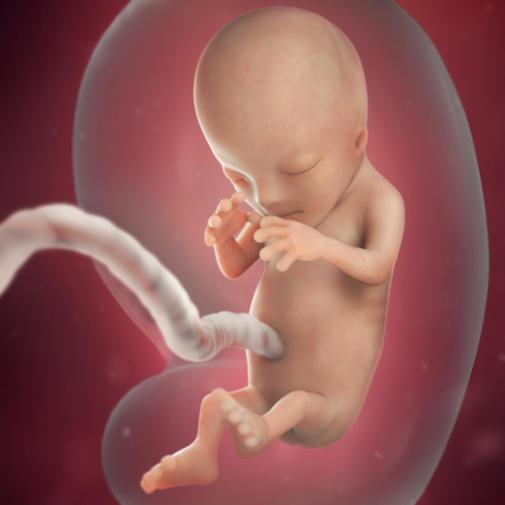

Vaše miminko už umí zatnout pěstičky, otevřít pusinku, polknout či zívat. Již je také jasně rozlišeno jeho pohlaví. Placenta přebírá plně úlohu výživy, nahrazuje tedy roli žlutého tělíska. Pocit na zvracení, který vás doteď mohl provázet, začne pomalu odeznívat. Stále se ale můžete cítit unavená.

V tomto týdnu přebírá plně výživu a zásobování kyslíkem placenta, trávicí systém dítěte dokáže vstřebávat glukózu. Utvářejí se mu hlasivky a pod blánou na očích se vyvíjí duhovka. Dozrávají chuťové buňky, začíná pracovat imunitní systém, hypofýza na spodině lebeční produkuje hormony. Vyvíjejí se vlasové váčky, ze kterých později vyrostou vašemu děťátku vlasy, v případě chlapce i vousy. Prstíky se oddělují, rostou na nich nehty a jemné ochlupení po celém těle. Kostra se zpevňuje. Pohlavní orgány nabývají své rysy. Dítě už se umí pohybovat, zatíná dlaň v pěst, umí otvírat ústa, zívat a sát. Dokonce se umí smát a cucat si palec.

Ve 12. týdnu těhotenství měří plod zhruba 5,5 cm.Při zjišťování délky plodu se měří vzdálenost od temene ke kostrči. Plod nyní váží zhruba 15 gramů.